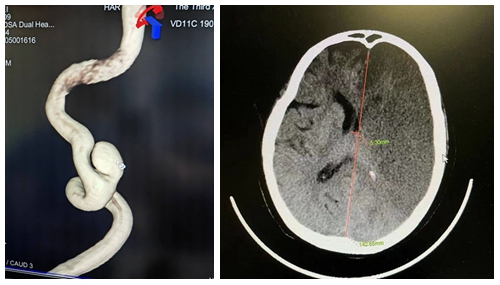

患者沈先生在外院行下颌骨肿瘤复发切除手术后颈部大血管出血,后并发大面积脑梗昏迷转至本院。入院CTA显示双侧顶枕叶大面积缺血梗塞灶,脑肿胀,左侧颈内动脉C1段动脉瘤。

任何一点处理不当,都可能导致患者死亡。最终团队经过综合研判决定首先以最快速度为患者行去骨瓣减压术保住性命。术后入神经外科重症监护病房,通过医护精心治疗于3月28日转入普通病房。接下来团队面对患者复杂病情冲破一道道难关,于5月6日在全麻插管下为患者行“左侧颈内动脉载瘤血管内血流导向支架置入术+弹簧圈动脉瘤栓塞术”。面对复杂扭曲的血管,仅仅耗时2小时就成功完成了手术。